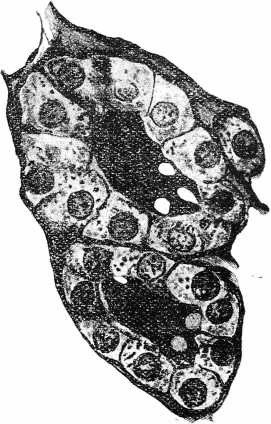

Переходя къ описанію своихъ наблюденіи, я позволяю себѣ прежде всего изложить строеніе нормальной щитовидной железы у тѣхъ видовъ животныхъ, надъ которыми производились наши опыты (кроликъ, кошка). Въ общемъ, на нашихъ препаратахъ оно представляется въ слѣдующемъ видѣ; щитовидная железа состоитъ изъ конгломерата множества железистыхъ пузырьковъ, заложенныхъ въ соединительно—тканную строму, богатоснабженную кровеносными сосудами и лимфатическими путями (см. табл. 1, рис. 1). Мѣстами между фолликулами заложены такъ называемыя солидныя скопленія эпи теліальныхъ элементовъ, представляющія, по-видимому, болѣе молодыя железистыя клѣтки, изъ которыхъ лишь со временемъ развиваются фолликулы. Форма фолликуловъ по большей части круглая, яйцевидная, мѣстами неправильно угловатая. Величина ихъ колеблется: есть очень маленькіе, стѣнка которыхъ въ разрѣзѣ представляется ограниченной всего 4—5 эпителиальними клѣтками, и наряду съ ними встрѣчаются очень большіе, ограниченные большимъ количествомъ клѣтокъ, причемъ распредѣленіе большихъ и малыхъ фолликуловъ между собой, повидимому, не подчиняется никакимъ особымъ законамъ. Намъ никогда не приходилось находить признаваемой нѣкоторыми авторами, по аналогіи съ другими железами, membranam рrорrіаm фолликуловъ. Эпителіальныя клѣтки фолликуловъ располагаюсъ или непосредственно на кровеносныхъ капиллярахъ и лимфатическихъ путяхъ, или на окружающихъ фолликулы соединительно-тканныхъ волокнахъ, что въ особенности легко удается доказать при окраскѣ по способу Joris’а. Пузырьки содержатъ коллоидную массу, представляющую двѣ разновидности, а именно, болѣе темную, легче воспринимающую красящія вещества, и свѣтлую, менѣе окрашиваемую. Эта коллоидная масса то вплотную прилегаетъ къ выстилающему фолликулъ эпителію, то, повидимому, въ зависимости отъ свертыванія подъ вліяніемъ фиксажа, отстаетъ отъ стѣнокъ фолликула, сохраняя лишь кое-гдѣ связь съ фолликулярными клѣтками въ видѣ тонкихъ мостиковъ. Въ лимфатическихъ сосудахъ, окружающихъ фолликулы, попадаются массы, похожія на только-что описанное коллоидное содержимое фолликуловъ. Фолликулярное содержимое не всегда является чистымъ и свободнымъ отъ примѣси; встрѣчаются въ разныхъ мѣстахъ препарата въ небольшомъ количествѣ десквамированныя эпителіальныя клѣтки, распавшіяся ядра клѣтокъ и красныя кровяныя тѣльца. Эпителіальныя клѣтки имѣютъ то нѣсколько уплощенную, то кубическую форму съ очень ясно различаемыми границами. Протоплазма клѣтки зерниста, при чемъ въ части, обращенной къ просвѣту фолликула, часто зернистость представляется рѣзче выраженной, и потому, клѣтка въ этомъ отдѣлѣ интенсивнѣе окрашивается. Въ кубическихъ клѣткахъ ядро лежитъ нѣсколько эксцентрично, въ наружной половинѣ клѣтки съ ясно выраженной хроматиновой сѣтью и отчетливо выступающими ядрышками. Ядра имѣютъ сферическую или нѣсколько вытянутую форму. Описываемыя клѣтки составляютъ большинство и, на первый взглядъ, кажутся единственными клѣтками фолликуловъ, почему и получили названіе главныхъ клѣтокъ. Въ перемежку съ ними, но въ меньшемъ количествѣ расположены такъ называемыя коллоидныя клѣтки, которыхъ у кролика очень мало. Эти клѣтки отличаются болѣе интенсивной окраской и гомогенной протоплазмой. Между обоими видами клѣтокъ существуетъ цѣлый рядъ переходныхъ формъ, протоплазма которыхъ также сильнѣе окрашивается, чѣмъ обыкновенныя главныя клѣтки, но въ значительной степени сохраняютъ зернистое строеніе.

Рис. 1. Срѣзъ изъ щитовидной железы нормальной кошки. Фиксація въ 10% формалинѣ, окраска по vаn Gіеsоn’y. Увеличеніе: Leitz. Осniar 4. Objest. 6.